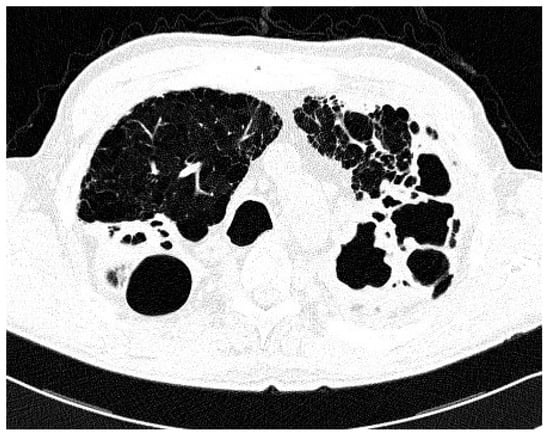

| Type of Chest CT Changes | Total Population No. 36 | NTM-LD No. 17 | Colonization No. 19 | p |

| Nodular/bronchiectasis No. (%) | 17 (47) | 8 (47) | 9 (47) | 0.03 |

| Infiltrations/cavities No. (%) | 6 (17) | 6 (35) | 0 (0) | |

| Non-specific No. (%) | 13 (36) | 3 (18) | 10 (57) | |